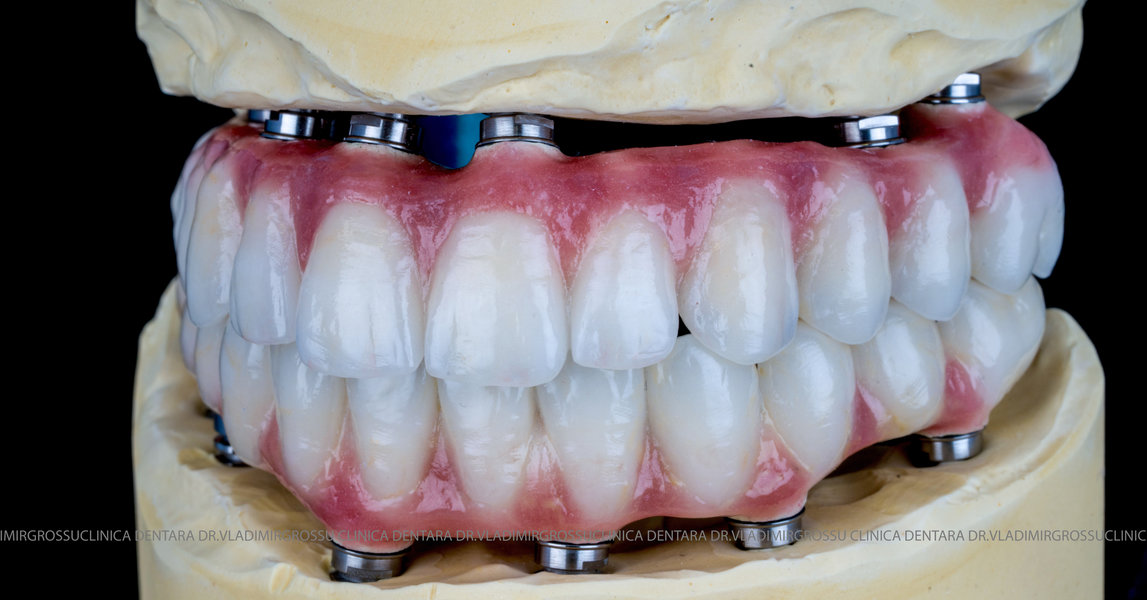

Cazuri clinice conceptul All-on-6